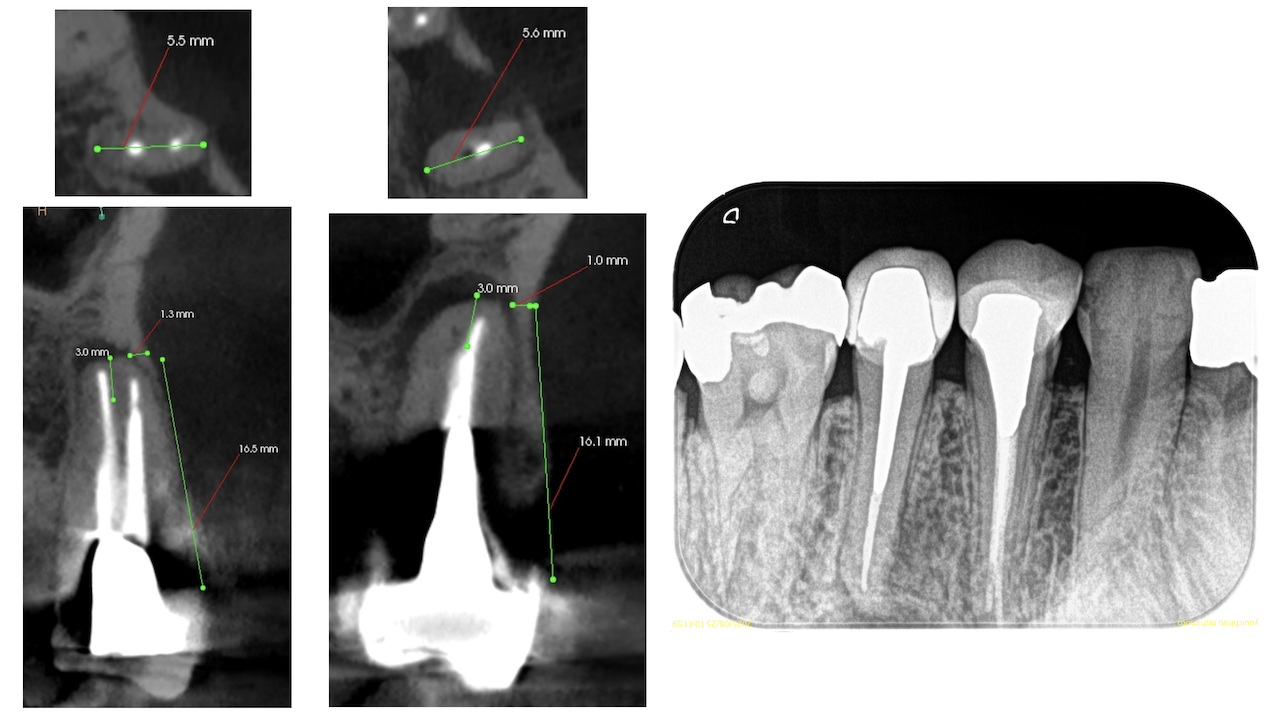

PA(2025.8.25)

#13のポストは長くテーパー型だが除去には時間を要するだろう。

OPG(2025.8.25)

術後にPA, CBCTを撮影した。

#12

#13